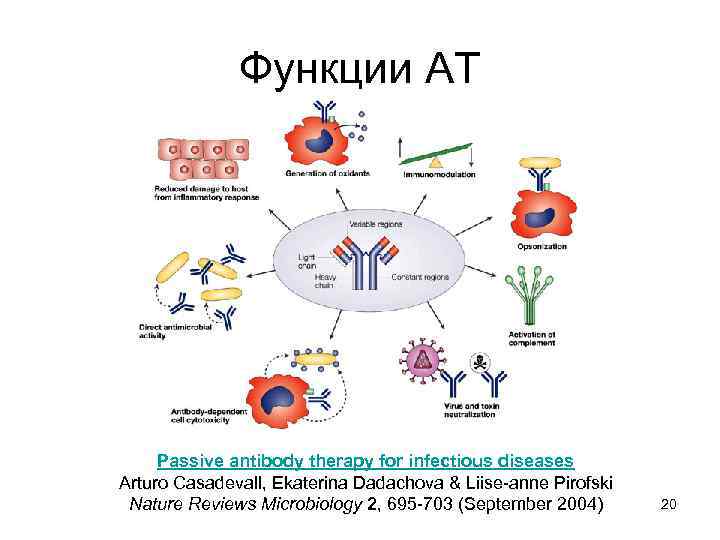

Функции АТ Passive antibody therapy for infectious diseases Arturo Casadevall, Ekaterina Dadachova & Liise-anne Pirofski Nature Reviews Microbiology 2, 695 -703 (September 2004) 20

Функции АТ Passive antibody therapy for infectious diseases Arturo Casadevall, Ekaterina Dadachova & Liise-anne Pirofski Nature Reviews Microbiology 2, 695 -703 (September 2004) 20